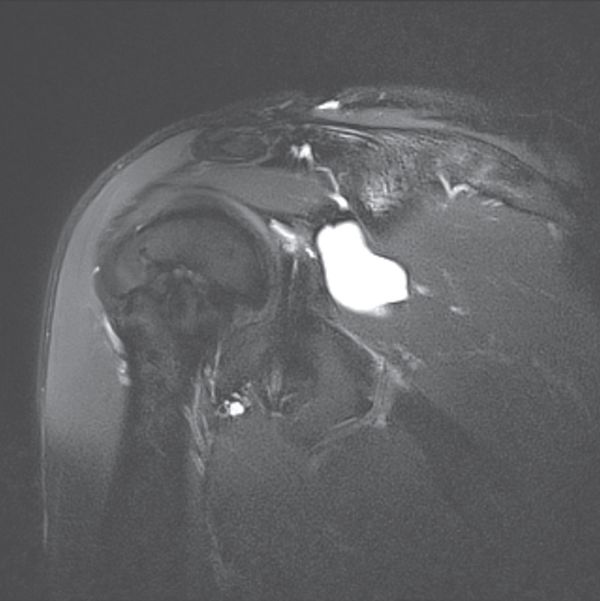

Examinations using intra-articular injection of a contrast medium (CT and MRA) are more reliable than simple MRI to visualize labral lesions and articular rotator cuff lesions (Figures).

Magnetic resonance arthrography (MRA) finding

Magnetic resonance arthrography (MRA) is standard, because it can also reveal the possible presence of a paraglenoid cyst (Figure) communicating with a labral tear, while allowing analysis of any concomitant tears (rotator cuff, osteochondral), and eliminate other causes of pain (acromioclavicular arthropathy, subacromial bursitis, tears relating to a painful and unstable shoulder).

Reliability depends on both machine and operator efficacy, but Jung et al. report a sensitivity of 85% and a specificity of 86% for superior labral tears.[41]